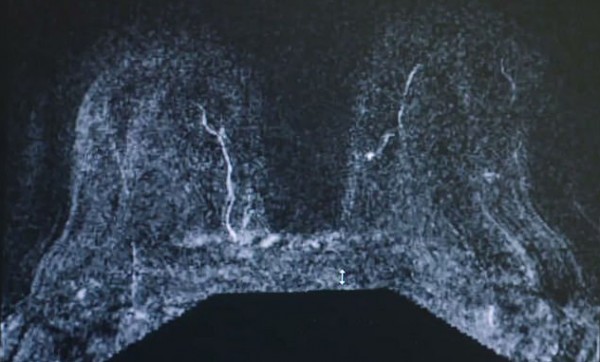

قررت سيدة أمريكية، أن تبث عملية جراحية خضعت لها لإزالة ورم خبيث من أحد ثدييها، لمتابعيها عبر موقع التواصل الاجتماعي "فيس بوك" من أجل توعية الأخريات.

وبحسب صحيفة "ديلي ميل"، شخّص الأطباء إصابة سونيا جونسون صاحبة الـ 50 عامًا بسرطان الثدي، ما جعلها تخضع لعملية جراحية لاستئصال الورم الخبيث من صدرها.